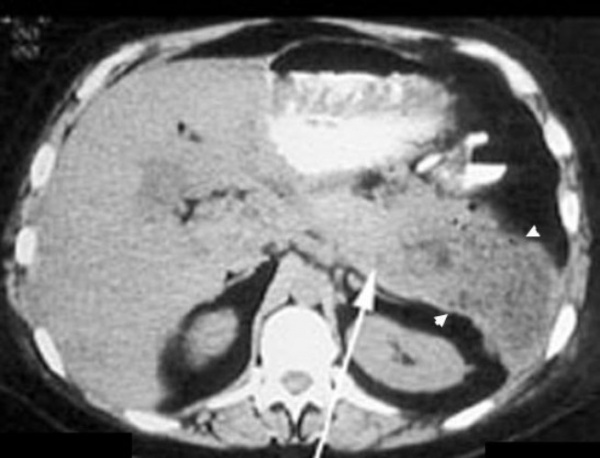

ПК локализовались в теле ПЖ у 7 (30,4%) пациентов, в хвосте ПЖ — у 7 (30,4%), в головке ПЖ — у 6 (26,2%) (рис. 1). Рис. 1. Псевдокиста головки поджелудочной железы (изображение при ультразвуковом исследовании). Стрелками указаны полость псевдокисты (1), бессосудистая зона (2). The arrows indicate pseudocyst cavity (1), avascular zone (2). У 3 (1%) больных имело место сочетанное расположение ПК в головке и теле ПЖ.

КТ органов брюшной полости. Псевдокиста поджелудочной железы у пациента после приступа острого панкреатита